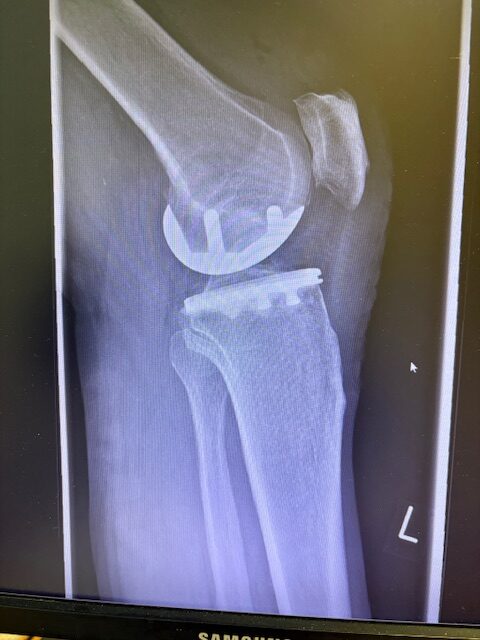

Η επέμβαση πραγματοποιήθηκε με ελάχιστα επεμβατική προσπέλαση και τοποθέτηση πρόθεσης μόνο στον έσω μηροκνημιαίο διαμέρισμα του γόνατος.

Η ακριβής προσαρμογή του εμφυτεύματος επιβεβαιώθηκε διεγχειρητικά, εξασφαλίζοντας σταθερότητα και φυσική κίνηση της άρθρωσης.

Στον ασθενή τα εμφυτεύματα που χρησιμοποιήθηκαν είναι της εταιρείας Zimmer-Biomet Persona Μηριαίο μέγεθος 6, κνημιαίο μέγεθος Η και ενθέμα (inlay) Η li. 8mm.